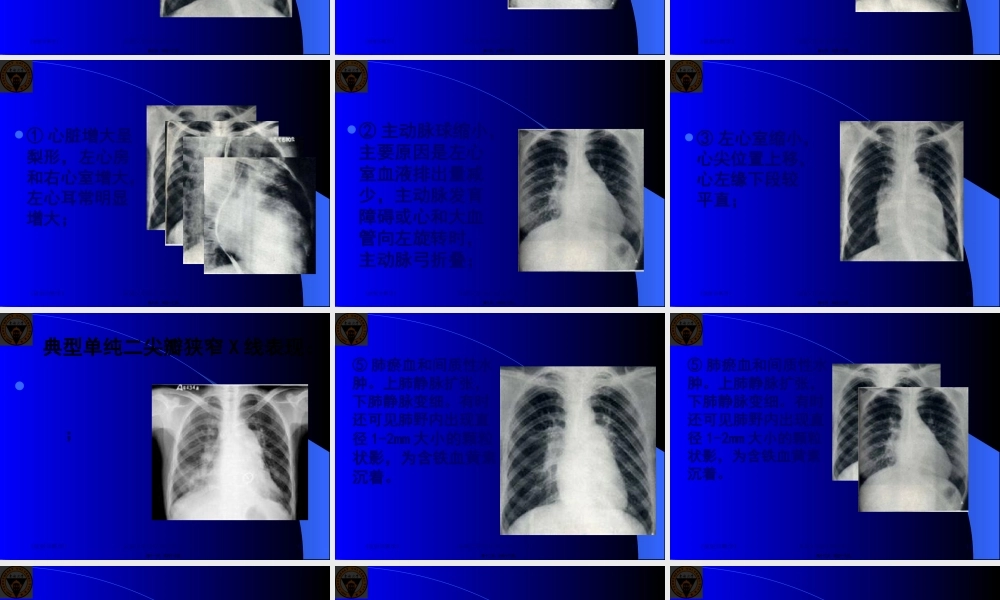

风湿性心脏病(rheumaticheartdisease)为常见心脏病之一。多发生于20-40岁,女性略多。各个瓣膜均可损害,但以二尖瓣为常见,其次为主动脉瓣及三尖瓣,而肺动脉瓣少见。《放射诊断学》1东南大学医学影像学系杨小庆第一页,共四十三页。一、二尖瓣狭窄二尖瓣狭窄(mitralstenosis)的主要病理改变为瓣环瘢痕收缩,瓣叶增厚融合,瓣膜外表粗糙硬化,有小赘生物以及腱索缩短和粘连。《放射诊断学》2东南大学医学影像学系杨小庆第二页,共四十三页。二尖瓣狭窄时,左心房的血液进入左心室发生障碍,左心房内压力升高,左心房扩张和肥厚,继而右心室扩大并出现肺瘀血现象。长期的二尖瓣狭窄,使左心室内血流量减少,左心室及主动脉均可萎缩。《放射诊断学》3东南大学医学影像学系杨小庆第三页,共四十三页。临床上轻度二尖瓣狭窄,病症不明显或主要为劳累后心悸。重度狭窄那么可出现咯血、端坐呼吸、肝大、下肢水肿等。主要体征为心尖区舒张期隆隆样杂音,肺动脉瓣区第二音亢进。《放射诊断学》4东南大学医学影像学系杨小庆第四页,共四十三页。①心脏增大呈梨形,左心房和右心室增大,左心耳常明显增大;《放射诊断学》5东南大学医学影像学系杨小庆第五页,共四十三页。①心脏增大呈梨形,左心房和右心室增大,左心耳常明显增大;《放射诊断学》6东南大学医学影像学系杨小庆第六页,共四十三页。①心脏增大呈梨形,左心房和右心室增大,左心耳常明显增大;《放射诊断学》7东南大学医学影像学系杨小庆第七页,共四十三页。①心脏增大呈梨形,左心房和右心室增大,左心耳常明显增大;《放射诊断学》8东南大学医学影像学系杨小庆第八页,共四十三页。②主动脉球缩小,主要原因是左心室血液排出量减少,主动脉发育障碍或心和大血管向左旋转时,主动脉弓折叠;《放射诊断学》9东南大学医学影像学系杨小庆第九页,共四十三页。③左心室缩小,心尖位置上移,心左缘下段较平直;《放射诊断学》10东南大学医学影像学系杨小庆第十页,共四十三页。典型单纯二尖瓣狭窄X线表现:;《放射诊断学》11东南大学医学影像学系杨小庆第十一页,共四十三页。⑤肺瘀血和间质性水肿。上肺静脉扩张,下肺静脉变细。有时还可见肺野内出现直径1-2mm大小的颗粒状影,为含铁血黄素沉着。《放射诊断学》12东南大学医学影像学系杨小庆第十二页,共四十三页。⑤肺瘀血和间质性水肿。上肺静脉扩张,下肺静脉变细。有时还可见肺野内出现直径1-2mm大小的颗粒状影,为含铁血黄...

蜗牛文库的最新文档

二年级数学下册其中检测卷二年级数学下册其中检测卷附答案#期中测试卷.pdf

10.00金币